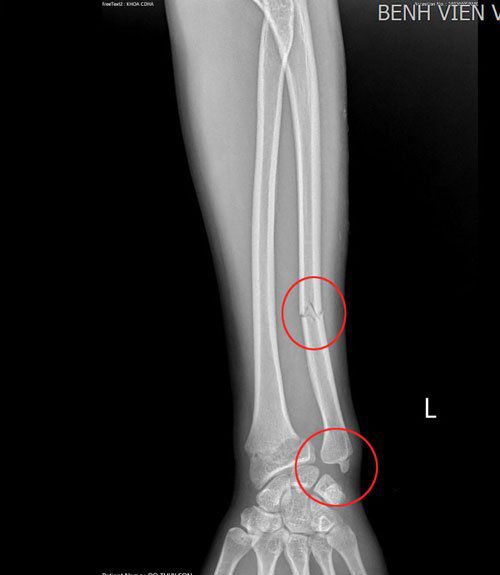

Hình ảnh gãy xương của cô gái do áo chống nắng cuốn vào bánh xe. Ảnh: BVCC.

Thông tin từ BV Việt Nam - Thụy Điển Uông Bí (Quảng Ninh) cho biết, một người phụ nữ 28 tuổi, vừa nhập viện cấp cứu vì bị ngã do áo chống nắng cuốn vào bánh xe máy khi đang di chuyển. Qua chụp chiếu, nữ bệnh nhân này bị gãy tay, hiện đã được phẫu thuật, tình hình sức khỏe ổn định và tiếp tục được theo dõi.